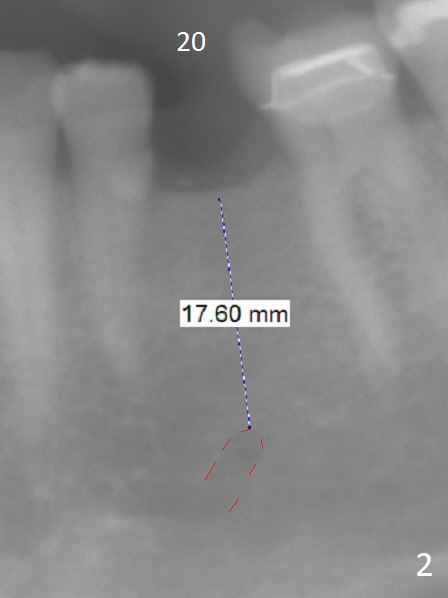

A 54-year-old woman has good oral hygiene. Panoramic X-ray shows generalized long roots, which suggest bruxism (Fig.1). Since the bone height is sufficient, a long implant will be placed, probably 4x13 mm (Fig.2). Take photos of the edentulous space, concentrating on the ridge top. Flap surgery will be performed. Crestal bone is going to be reduced if the ridge is narrow. PA is taken after 1.6 mm drill for 11 mm. If the trajectory is correct, a 3.3 mm Magic Drill is to be used (13 mm stopper, after Marking bur), followed by 4x11 mm dummy implant. If the bone is dense, a final drill will be used for 14 mm before placement of the definitive implant. The harvested autogenous bone will be placed around a pair abutment to increase the buccolingual width. Take postop photos to show the ridge augmentation.